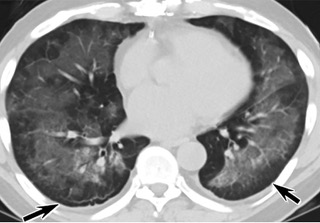

![6AYɨCTfʹ_ܤ]nt]QacT(ïfCT_)](./W020210804330783485235.jpeg)

ݐ6AYɨCTfʹ_ܤ]nt]QacT(ïfCT_)